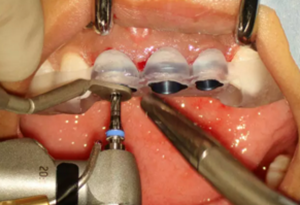

(2)即刻種植、即刻臨時修復(fù)。術(shù)中不翻瓣微創(chuàng)拔除牙根,牙槽 窩骨壁完整。在多級導(dǎo)板輔助下完成種植窩洞制備,植入Bego柱形種植 體,型號分別為:上頜右側(cè)中切牙位點4.1mm×15mm、上頜左側(cè)中切牙 位點?3.75mm×15mm、上頜左側(cè)側(cè)切牙位點3.25mm×15mm,扭矩均為 35N·cm。種植體與唇側(cè)骨壁間隙約2mm,植入Bio-Oss®Collagen骨膠 原。戴入橋用鈦臨時基臺,臨時冠就位順利,自凝樹脂口內(nèi)粘接后適當(dāng)修整 外形,充分磨光,調(diào) 至正中 、前伸 和側(cè)方 與對頜牙均無接觸。術(shù)后 根尖片顯示種植體位置、方向良好。

圖8 導(dǎo)板輔助下備洞

圖9 植入種植體